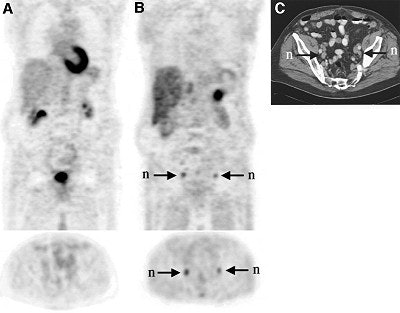

| The 73-year-old patient shown above had an increasing serum PSA value of 9.1 ng/mL, two years after undergoing external beam radiation therapy. Coronal and transaxial FDG-PET images (A) show no uptake in prostate and pelvic lymph nodes. The coronal and transaxial AC-PET images (B) show bilateral high uptake in the iliac lymph nodes. The CT scan shows corresponding 1.5-cm iliac nodes (n). Image and caption courtesy of Dr. Nobuyuki Oyama and the Journal of Nuclear Medicine. |